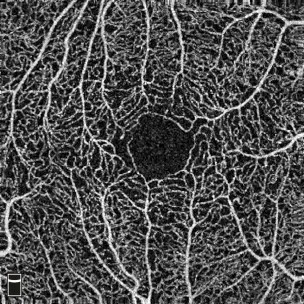

retina image taken by OCT imaging technology

Optical Coherence Tomography Angiography: superficial later of retina – courtesy of Edinburgh Imaging Facilities

Diabetic retinopathy is a clinically well-defined, sight threatening, chronic microvascular complication that eventually affects virtually all people with diabetes. It represents one of the major causes of blindness in the world. Progression of retinopathy is related to hyperglycaemia but it is known that rapid improvement of hyperglycaemia in people with diabetes, may paradoxically lead to a progression of diabetic retinopathy at least in the short term. Therapies associated with improvement in hyperglycaemia include insulin pump therapy and islet transplantation. However the impact of such therapies on the progression of diabetic retinopathy have not been well studied particularly in relation to the stabilisation of their glycaemic control. We aim to examine prospectively a cohort of subjects preceding commencement of insulin pump/islet transplantation at regular intervals for 1 year. Retinal screening along with novel assessments of the retinal vessels using Optical Coherence Tomography Angiography (OCTA) will be performed alongside assessments of metabolic control (HbA1c) and Continuous Glucose Monitoring Systems (CGMS), the latter allowing an assessment of glycaemic lability. The SCI-Diabetes programme will be utilised to retrospectively examine eye disease pre and post commencement of insulin pump therapy in Lothian with an emphasis on changes noted over the first year of therapy.